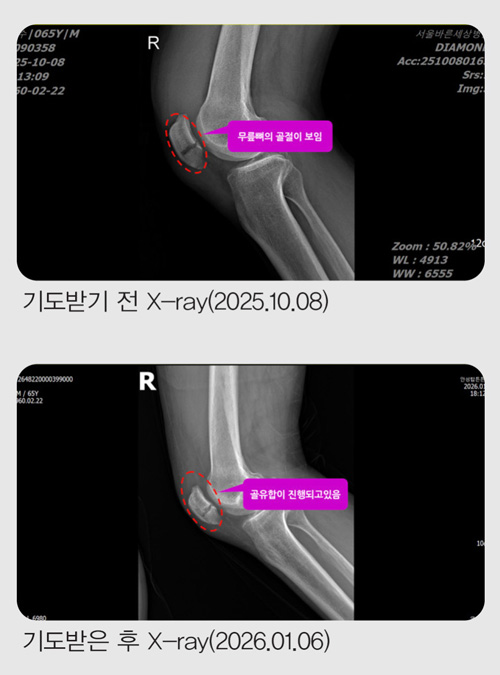

¹«¸»À °ñÀý ¼ö¼ú À§±â¿¡¼ 6ÀÏ ¸¸¿¡ Ä¡·á¹Þ¾Ò½À´Ï´Ù

ÀÛ³â 10¿ù 8ÀÏ ¼ö¿äÀÏ, Ãß¼® ¿¬ÈÞ¸¦ ¸Â¾Æ ¸ðó·³ °¡Á·µé°ú ÇÔ²² ºÏÇѻ꿡 ¿Ã¶ú½À´Ï´Ù.

»êÇàÀ» ½ÃÀÛÇÑ Áö ¾à 15ºÐÂë Áö³µÀ» ¶§, »ÏÁ·ÇÏ°Ô Æ¢¾î³ª¿Â µ¹¸æÀÌ¿¡ ¿ÞÂÊ ¹ß¸ñÀÌ °É·Á ³Ñ¾îÁ³½À´Ï´Ù.

´Ù½Ã ÀϾ »êÀ» ¿À¸£·Á ÇßÁö¸¸ ¹«¸À» Â´Â µíÇÑ ±Ø½ÉÇÑ ÅëÁõ¿¡ ´õ ÀÌ»ó ÇÑ ¹ß¦µµ ¿òÁ÷ÀÏ ¼ö ¾ø¾î °á±¹ »êÀ» ³»·Á¿Í¾ß Çß½À´Ï´Ù. ³»·Á¿À´Â ±æÀº »êÇຸ´Ù ÈξÀ ´õ °íÅ뽺·¯¿ü½À´Ï´Ù. µÎ ¼ÕÀ» ¹Ù´Ú¿¡ ¤°í °è´ÜÀ» ÇÑ °è´Ü¾¿, ÇÑ ¹ß·Î °£½ÅÈ÷ ³»·Á¿Í °Ü¿ì Åýÿ¡ ¸öÀ» ½ÇÀ» ¼ö ÀÖ¾ú½À´Ï´Ù.

Åýà ¾È¿¡¼ ¹«¸À» ¸¸Áö´Â ¼ø°£, »À°¡ ºÎ·¯Á³´Ù´Â °ÍÀÌ ºÐ¸íÈ÷ ´À²¸Á³½À´Ï´Ù.

Áý ¾Õ¿¡ µµÂøÇßÁö¸¸ ÇÑ ¹ß¦µµ °È±â Èûµé¾î ´Ù½Ã Åýø¦ Ÿ°í ±Ùó °³ÀÎ º´¿øÀ¸·Î °¬°í, °ð¹Ù·Î Å« º´¿ø ÀÀ±Þ½Ç·Î À̵¿Ç϶ó´Â ¸»À» µé¾ú½À´Ï´Ù.

ÀÀ±Þ½Ç¿¡¼ MRI¸¦ ÃÔ¿µÇÑ µÚ, ÀÇ»ç ¼±»ý´ÔÀº "¹«¸»À°¡ °ñÀýµÆ½À´Ï´Ù. ¹«¸Àº ÀÏ¹Ý »À¿Í ´Þ¸® À§¾Æ·¡°¡ ºÐ¸®µÅ ÀÖ¾î ¹Ýµå½Ã ¼ö¼úÀÌ ÇÊ¿äÇÕ´Ï´Ù"¶ó°í ¸»Çß½À´Ï´Ù.

ÀÌ¾î ¼ö¼úÀ» ÇÏ´õ¶óµµ ¸ñ¹ß »ç¿ë°ú ÀçȰ Ä¡·á°¡ ÇÊ¿äÇÏ´Ï 10¿ù 10ÀÏ ±Ý¿äÀÏ¿¡ ¼ö¼úÀ» ÇÏÀÚ°í ±ÇÇß½À´Ï´Ù.

±×·¯³ª ÀÔ¿øÇØ ¼ö¼úÀ» ¹Þ°Ô µÇ¸é 10¿ù 12ÀÏ¿¡ ÀÖ´Â ±³È¸ ⸳ 43Áֳ⠱â³ä ¿¹¹è¿¡ Âü¼®ÇÒ ¼ö ¾ø¾ú½À´Ï´Ù. Àú´Â ¹ÏÀ½À¸·Î Ä¡·á¹Þ°íÀÚ ÀÔ¿øÀ» ¼±ÅÃÇÏÁö ¾Ê°í ÁýÀ¸·Î µ¹¾Æ¿Ô½À´Ï´Ù.

10¿ù 14ÀÏ, °ñÀýµÈ Áö 6ÀÏ ¸¸¿¡ Á¤Çü¿Ü°ú¸¦ ã¾Æ X-ray¸¦ Âï¾ú½À´Ï´Ù.

ÀÇ»ç´Â "»À°¡ °ÅÀÇ ´Ù Àß ºÙ¾ú½À´Ï´Ù. ÀÌÁ¦ °ü¸®¸¸ ÀßÇÏ½Ã¸é µË´Ï´Ù"¶ó°í ¸»Çß½À´Ï´Ù.

ÀÏ¹Ý »Àº¸´Ù Ä¡·á°¡ ±î´Ù·Î¿î ¹«¸»À°¡ ºÒ°ú ¸çÄ¥ ¸¸¿¡ ºÙÀº °ÍÀÔ´Ï´Ù. ÇÒ·¼·ç¾ß!